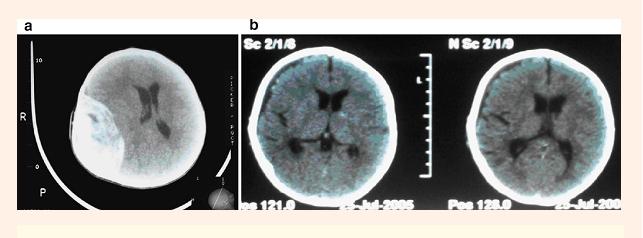

Traumatic epidural hematoma (EDH) represents a rare head injury complication in infants. Its diagnosis can be quite challenging because its clinical presentation is usually subtle and nonspecific. Authors present a study on 30 infants with epidural hematoma (EDH) admitted in the Pediatric Department of Neurosurgery of the "Bagdasar-Arseni" Clinical Hospital in the period of 1990-2007 (17 years). The most common symptom was irritability, which occurred in 16 cases (53.3%), of our patients. Pallor in all cases (100%) and subgaleal hematoma in 20/30 (66.6%) of the patients. These were the most common clinical signs that occurred upon admission; both of them represent signs of significant clinical importance. Surgical evacuation via craniotomy was required in 26/30 (86.6%) of our patients, while 4/30 (13.3%) of the patients were managed conservatively. The mortality rate was 6.6% in our series, whilst the long-term morbidity rate was 3.3%. EDH in infants represents a life-threatening complication of head injury, which requires early identification and prompt surgical or conservative management depending on the patient's clinical condition, the size of EDH, and the presence ofa midline structure shift on the head's CT scan.

创伤性硬膜外血肿(EDH)是婴儿罕见的头部损伤并发症。其诊断颇具挑战性,因为其临床表现通常不明显且无特异性。作者对1990年至2007年(17年)期间在“巴格达萨尔 - 阿尔塞尼”临床医院神经外科儿科收治的30例硬膜外血肿(EDH)婴儿进行了一项研究。最常见的症状是易激惹,在我们的16例患者(53.3%)中出现。所有病例(100%)均有面色苍白,20/30(66.6%)的患者有帽状腱膜下血肿。这些是入院时最常见的临床体征;两者均为具有重要临床意义的体征。我们26/30(86.6%)的患者需要通过开颅手术进行血肿清除,而4/30(13.3%)的患者采用保守治疗。我们系列研究中的死亡率为6.6%,长期发病率为3.3%。婴儿EDH是一种危及生命的头部损伤并发症,需要根据患者的临床状况、EDH的大小以及头部CT扫描中线结构是否移位,尽早识别并迅速进行手术或保守治疗。